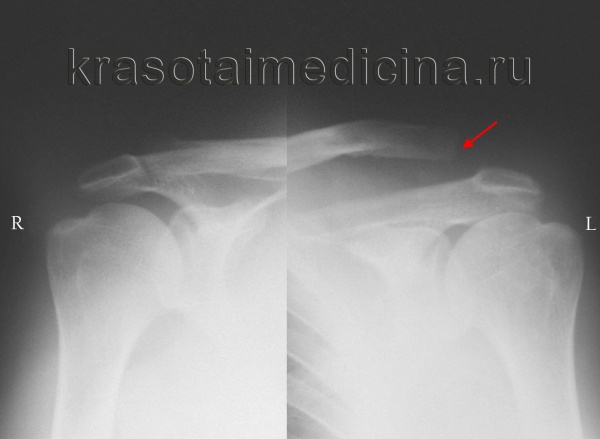

• Рентгенологическое исследование. Для подтверждения диагноза выполняется снимок акромиально-ключичного сустава или рентгенография грудино-ключичного сочленения. В случае неполных вывихов может потребоваться сравнительная рентгенограмма обеих сочленений, иногда с функциональной нагрузкой (пациент держит небольшой груз).

Рентгенография акромиально-ключичных суставов. Вывих акромиального конца левой ключицы (справа — норма для сравнения).